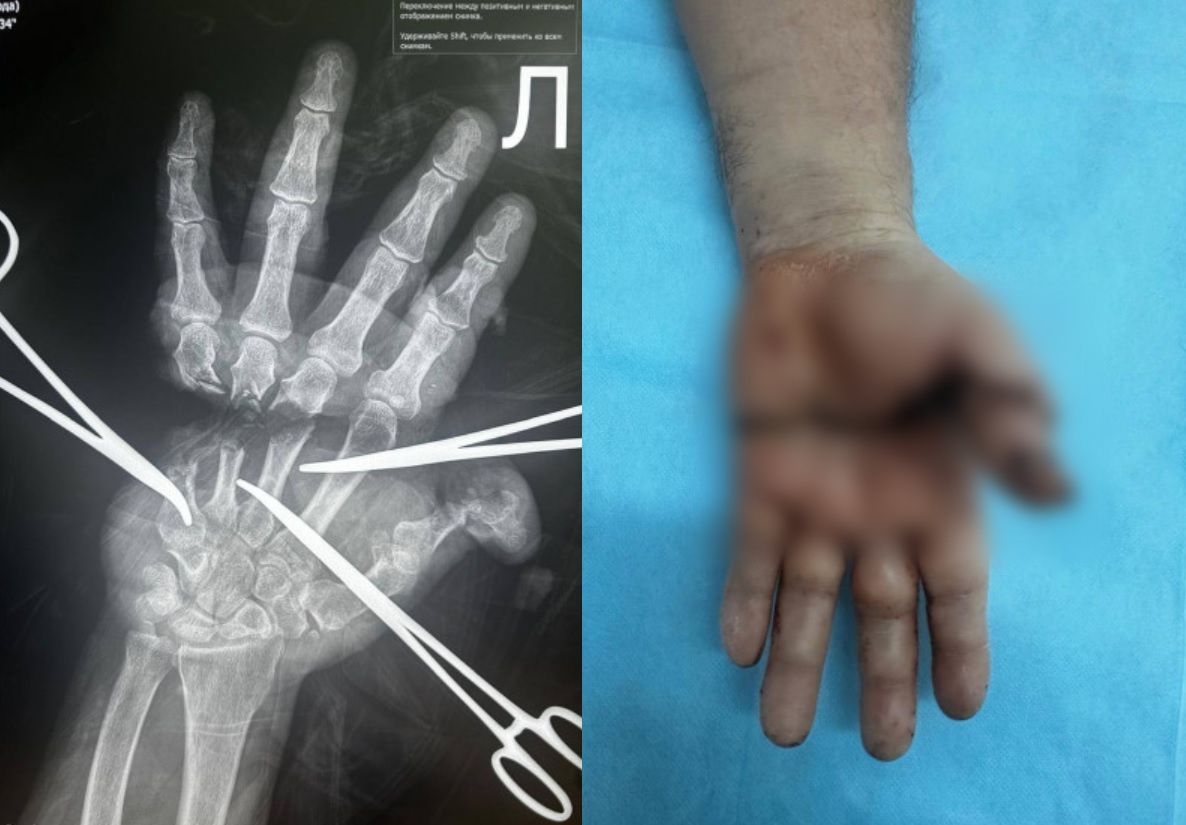

Фото минздрава НСО.

Сложный пациент с отрезанной кистью поступил недавно в Городскую клиническую больницу №34. Пострадавшего от неудачного взаимодействия с неназванным электроинструментом сибиряка привезли в ГКБ в 17:42, а уже через 18 минут начали оперировать. Медики решили делать сложную операцию — реплантацию.

Как рассказали в пресс-службе минздрава Новосибирской области, эта тонкая работа требовала слаженного взаимодействия микрохирургов, травматологов-ортопедов, анестезиологов-реаниматологов и операционных медсестер. В рамках операции необходимо было восстановить мельчайшие сосуды, нервы, сухожилия и кости. Успех зависит от степени повреждения тканей, времени поступления пациента (скорости оказания помощи), а также последующей реабилитации. В данном случае у мужчины есть шансы на восстановление работоспособности кисти.

«Операция длилась много часов и потребовала ювелирной точности. Врачи поэтапно восстановили поврежденные структуры, обеспечив жизнеспособность кисти. Теперь пациента ждет длительный процесс реабилитации, но главное – рука спасена. Реплантация конечностей – сложный и редкий вид хирургического вмешательства, который требует высокой квалификации и применения современных технологий», – прокомментировал главврач ГКБ №34 Ярослав Фролов.